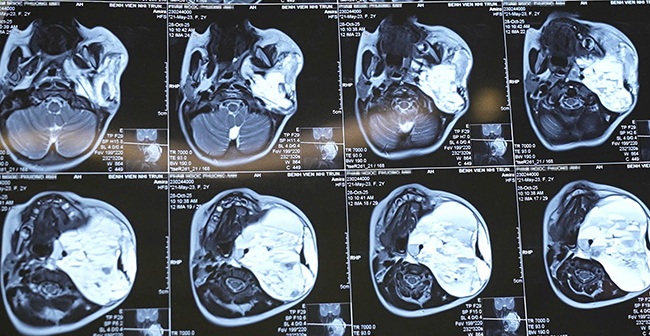

Khi được chuyển đến Bệnh viện Nhi Trung ương, tình trạng của bé P.A. diễn biến rất xấu. Trẻ suy hô hấp nặng, phải đặt nội khí quản và thở máy hỗ trợ. Kết quả chụp cộng hưởng từ (MRI) cho thấy khối u kích thước “khổng lồ” (86x101x99mm), chiếm tới 3/4 vùng cổ, đang chảy máu cấp tính bên trong. Khối u chèn ép, đẩy lệch hoàn toàn thanh quản, khí quản và thực quản, gây hẹp lòng thanh hầu, đe dọa trực tiếp tính mạng trẻ do nguy cơ suy hô hấp, suy tuần hoàn và mất máu cấp.

Hình ảnh khối u của bé P.A. Ảnh: BV Nhi Trung ương

Nhờ sự chỉ đạo quyết liệt, kịp thời của Ban Giám đốc Bệnh viện cùng sự phối hợp chặt chẽ của các chuyên khoa, quá trình điều trị, phẫu thuật đã diễn ra thuận lợi. Các bác sĩ bóc tách thành công toàn bộ khối u (kích thước thời điểm phẫu thuật lên tới 100x150mm), cắt bỏ hoàn toàn khối u khổng lồ, giải phóng chèn ép. Đặc biệt, không gây tổn thương bó mạch vùng cổ, bảo tồn nguyên vẹn toàn bộ các cấu trúc thần kinh và mạch máu quan trọng, đưa bệnh nhi trở về trạng thái sinh lý bình thường.